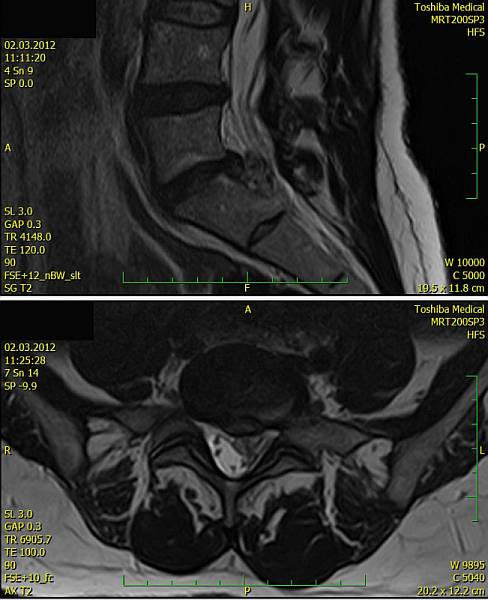

1. Žena, 48 let. Na MR patrná 8mm velká paramediální hernie L5/S1 vlevo s extruzí materiálu ploténky do epidurálního prostoru a útlakem kořenů L5 a S1 vlevo. Pacientce byla doporučena operace, kterou odmítla a zvolila alternativní postup s aplikací ozonu. Viz obr. 6a

Na kontrolním MR po 1 měsíci (po 2 aplikacích ozonu) periradikulárně je viditelné vymizení fragmentů v epidurálním prostoru a částečná retrakce meziobratlové ploténky. Subjektivně výrazná úleva, po 4 týdnech návrat do práce. Viz obr. 6b